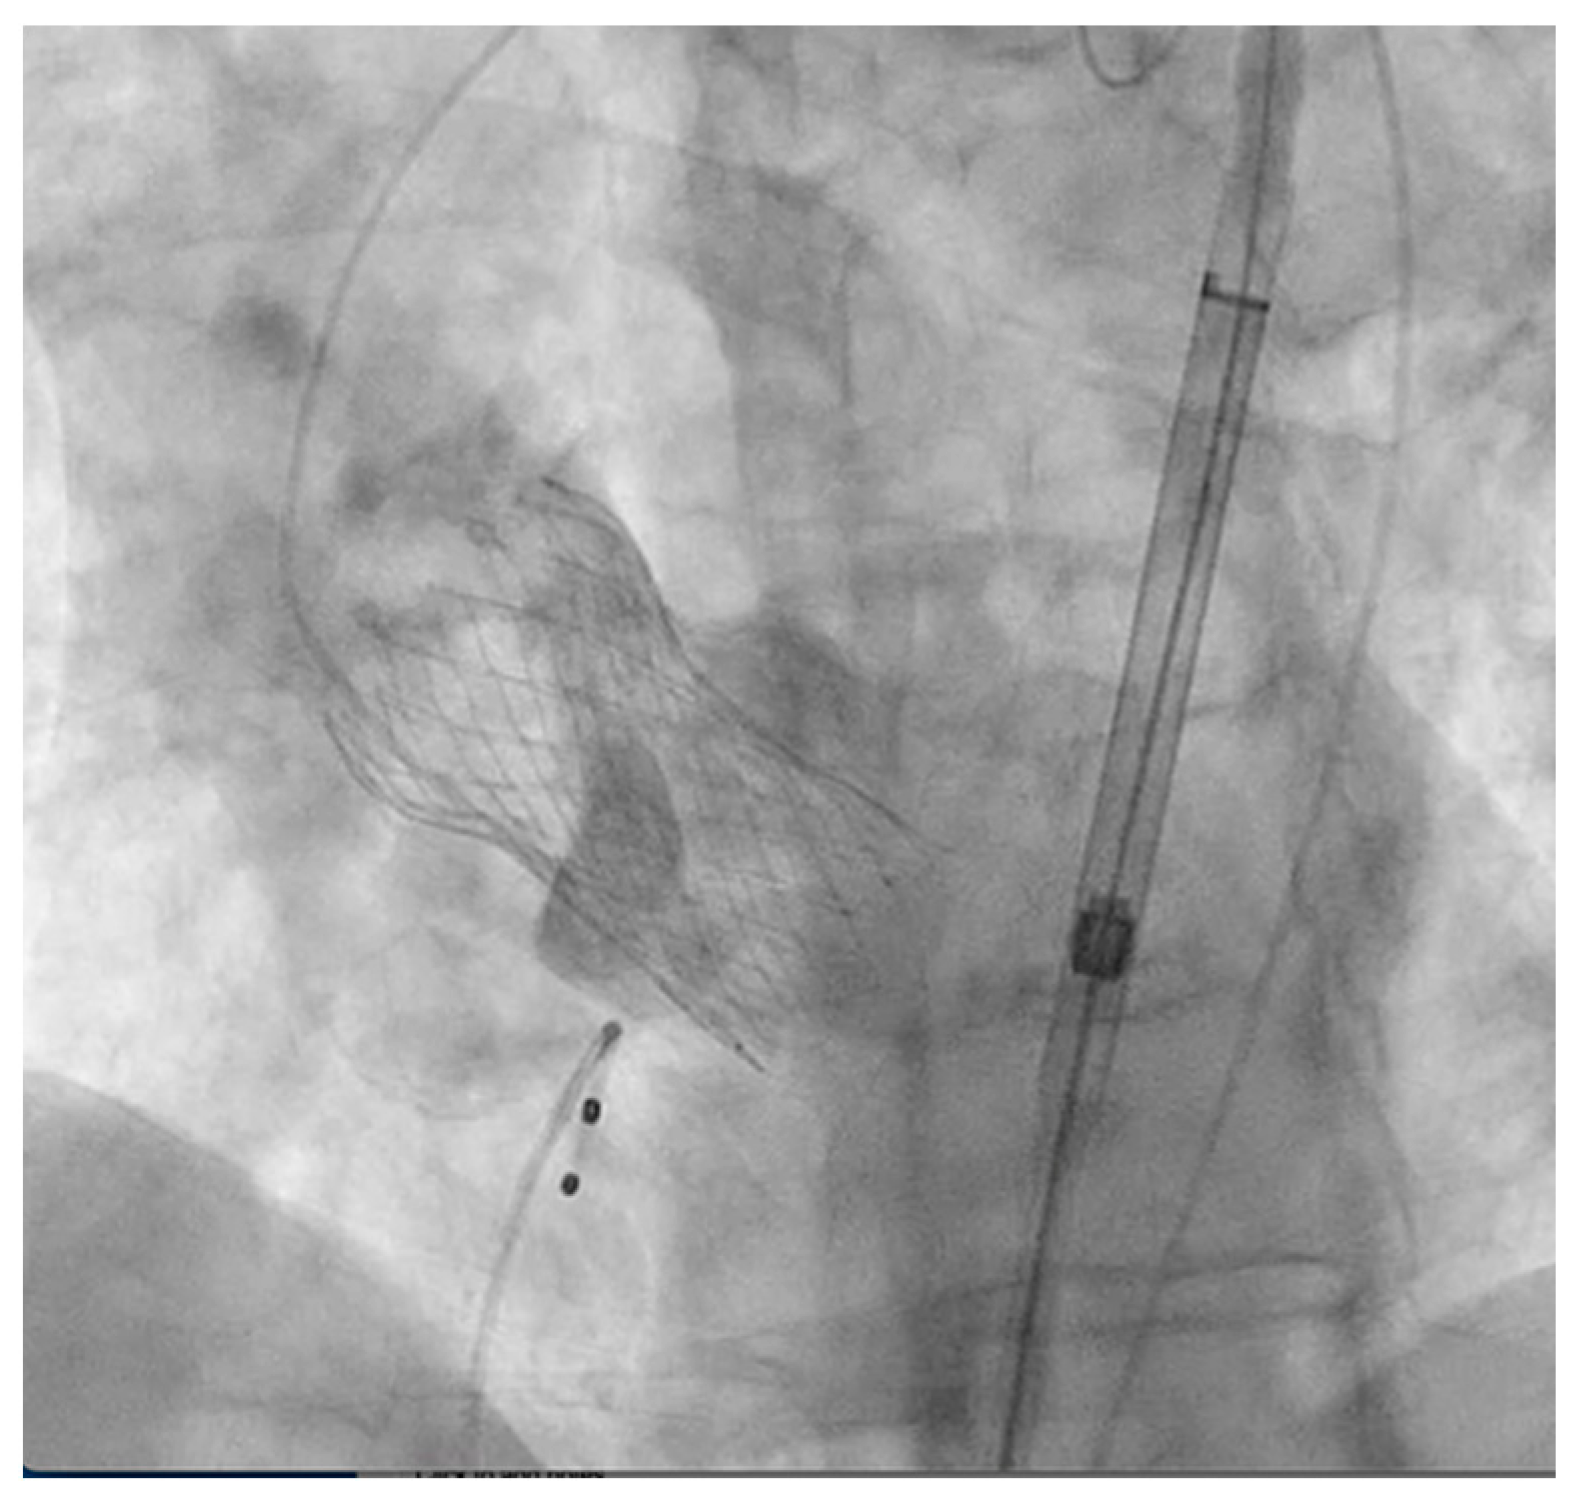

2. Detailed Case Description

3.1. Aortic Annular Rupture